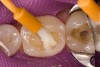

Figure 2